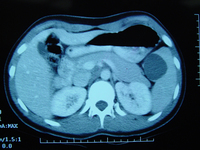

Tomografia computadorizada (TC) revelando abscesso intra-abdominal consistente com apêndice perfurado

Do acervo de Dr. KuoJen Tsao; usado com permissão